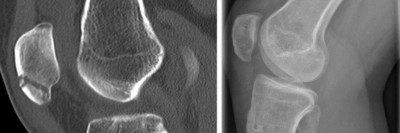

Warum nimmt die Oberschenkelschwellung beim Dialysepatienten immer mehr zu?

Bei einem 54-jährigen Mann nimmt seit einem halben Jahr die schmerzhafte Schwellung der rechten Hüfte bei bekannter Peritonealdialyse zu. Es besteht eine chronische Niereninsuffizienz. Vier Jahre zuvor war eine Parathyroidektomie bei tertiärem Hyperparathyreoidismus durchgeführt worden. Was zeigen Röntgen- und MRT-Bilder?